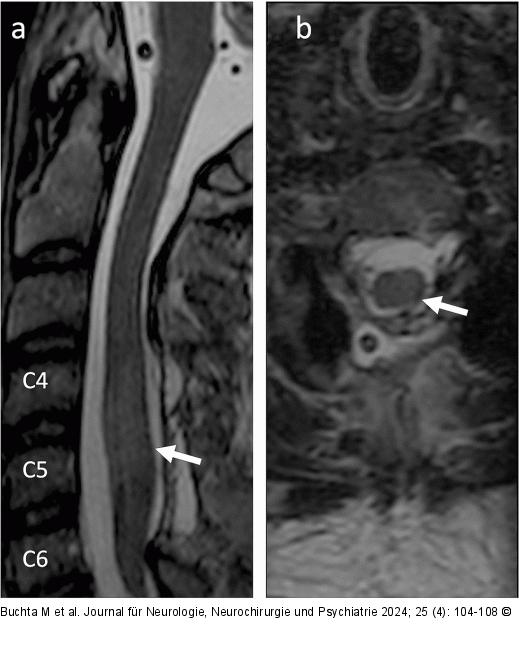

Abbildung 4a-b: Postoperatives MRT Das postoperative MRT der HWS zeigt ein sagittales T2-gewichtetes Bild (a) und ein axiales T2-gewichtetes Bild (b), das eine adäquate Dekompression des Spinalkanals mit einem rückläufigen Rückenmarksödem von C4 bis C6 zeigt (Pfeil). Es sind keine Anzeichen einer Restblutung erkennbar. (MRT: Magnetresonanztomographie; HWS: Halswirbelsäule) |

Abbildung 4a-b: Postoperatives MRT

Das postoperative MRT der HWS zeigt ein sagittales T2-gewichtetes Bild (a) und ein axiales T2-gewichtetes Bild (b), das eine adäquate Dekompression des Spinalkanals mit einem rückläufigen Rückenmarksödem von C4 bis C6 zeigt (Pfeil). Es sind keine Anzeichen einer Restblutung erkennbar. (MRT: Magnetresonanztomographie; HWS: Halswirbelsäule) |